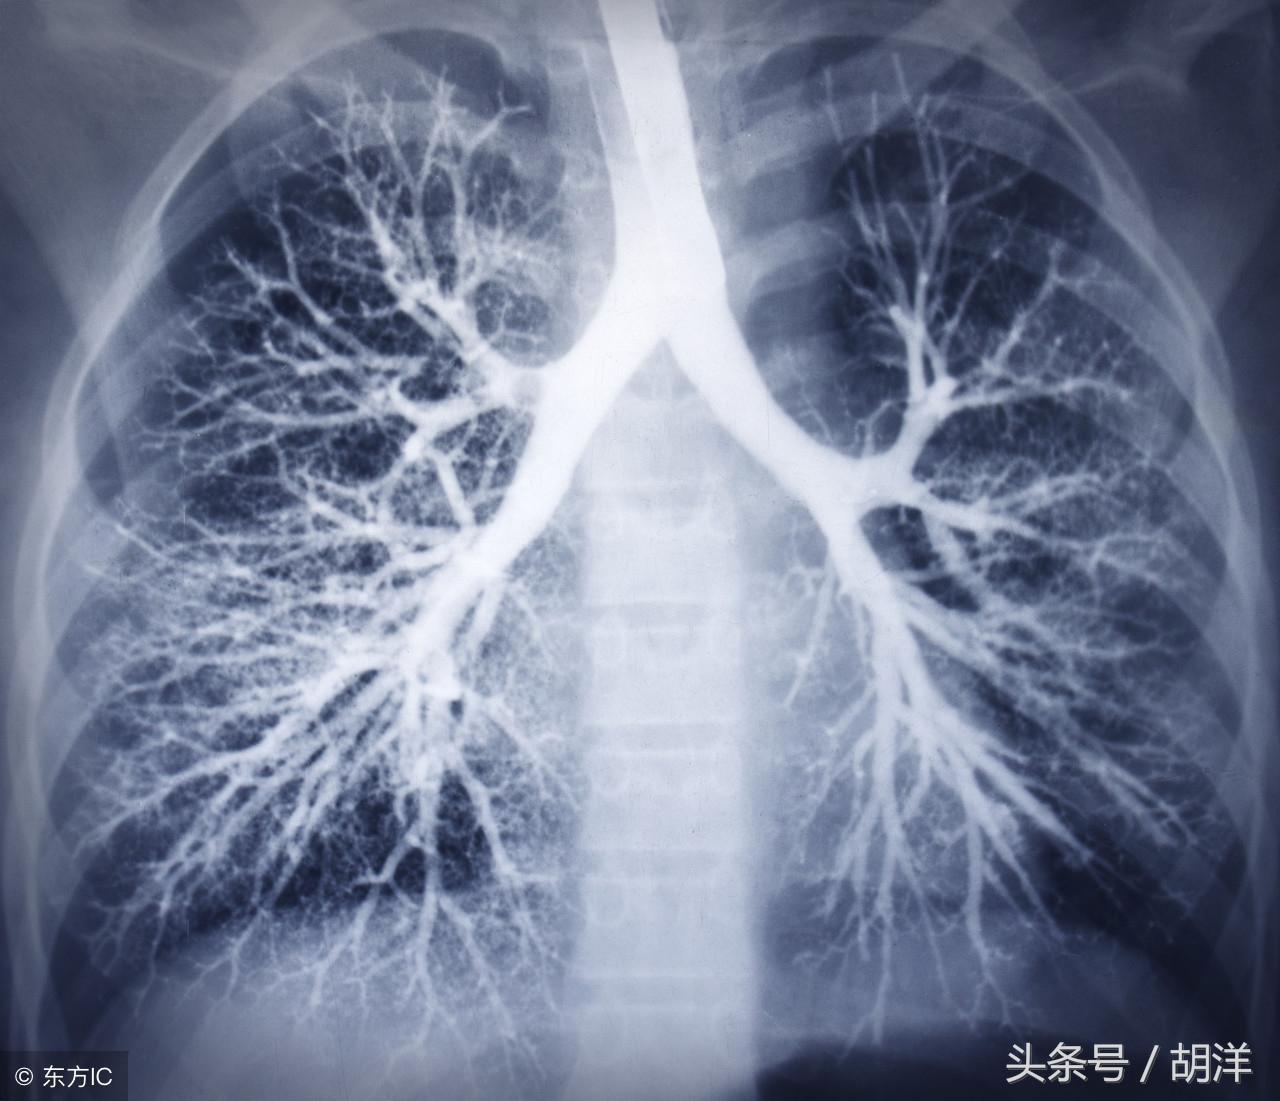

咳血又称咯血,是呼吸科一个比较严重的症状,由于其可能提示肺部肿瘤等严重疾病而受到重视,但事实上在引起咯血的病因中,肺部恶性肿瘤所占的比例并不是很大,但很多人因咯血而焦虑异常,特别是咯血久治不愈情况下,更加令人无法正常的生活和学习,那么哪些疾病可能导致反复发作痰中带血或者咳出满口鲜血呢?

支气管扩张是一种支气管管壁结构破坏性疾病,正常情况下,支气管是一个带有弹性,拥有一定管径的能够维持正常呼吸通气的结构,当管壁结构受到破坏时,气管会受到被动的牵拉而扩张,管壁的血管由于弹性较小,容易被撕扯呈血管瘤改变,一旦胸腔内血流压力增大可能冲破血管瘤变薄的管壁而导致大咯血,少量渗血时则呈现为痰中带血。

肺癌也是较为常见的导致咯血的原因,恶性肿瘤细胞对于肺组织的侵蚀是其他疾病无法比拟的,几乎可以侵犯肺部正常组织中的所有结构,包括血管,另外,肺癌癌肿由于生长过快,其表面的细胞可能会因为得不到充足的血液供应而坏死,这样的坏死很容易产生渗血,是引起痰中带血的常见原因。

曲霉菌是一种常见的真菌,正常情况下,曲菌很少感染肺部结构正常,免疫力良好的人群,当肺部受到破坏,特别是形成较大空洞和支气管扩张时,曲霉菌可以趁机进入空洞扩张的支气管内与其中渗出的白细胞、纤维素等成分形成球状结构,成为曲菌球,曲菌球在空洞内能够自由的活动,对空洞壁有机械性的损伤,当损伤到管壁变异的血管瘤时,极有可能导致大出血。